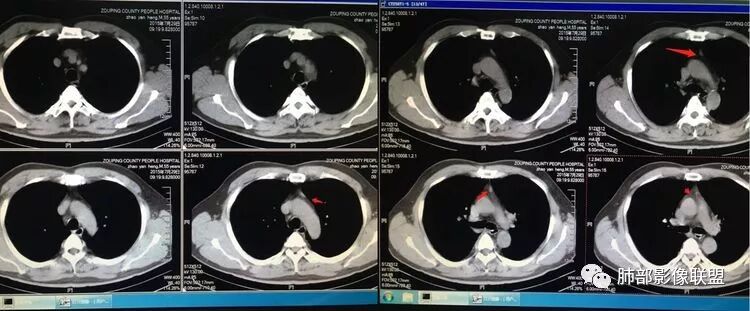

胸腺瘤(B2–C)型。中年男性,体检前上纵隔近奇静脉水平不规则呈生姜样占位,密度不均,延迟强化,进行性增大。

胸腺区实性占位,呈分叶状,病灶近一年间明显增大,增强扫描中度强化,病灶与周围组织界限模糊,考虑恶性,胸腺癌(鳞癌)。

男,59

2015年小,2019年增强,不规则强化不均匀。

48-60-70,28-30-24,不规则渐进性强化,密度不均。

诊断:侵袭性胸腺瘤

老年男性,15年胸腺区小结节,19年明显增大,边缘不整,明显分叶,增强后不均匀强化,考虑内部坏死,周围脂肪间隙模糊,考虑恶性,胸腺癌?

男性,59岁,无肌无力。前纵隔占位,偏侧,形态不规则,边缘分叶状,似有点状微钙化,病灶较前4年前增大,明显强化,考虑恶性,周围似见小淋巴结,倾向胸腺癌。

59M,前纵隔占位,肿瘤边缘分叶明显,其上缘见絮状改变,边缘见囊状低密度影(似位于肿块边缘),增强后实质成分见明显强化(以静脉期强化明显),内见可以血管影;四年时间增大明显,考虑胸腺来源偏恶性肿瘤,考虑神经内分泌肿瘤(如类癌)可能,胸腺癌待排。

因为原病灶没看到,现在原有位置有一大病灶,如果是新发的,原有病灶会推移一边,但是没看到,倾向于原病灶增大

根据强化,高的70HU,低的没测,考虑囊实性

实性部分明显强

偏一侧

上面来的血供,病灶深分叶

附近心包似乎也不干净

有淋巴结

从前后变化,病灶的形态、强化、附近的淋巴结、心包改变,支持恶性

结果

胸腺癌—非角化鳞状细胞癌